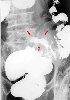

A operated case of diverticular abscess of the sigmoid colon.

X-ray

Diverticulum/Diverticulitis, Peridiverticular Abscess